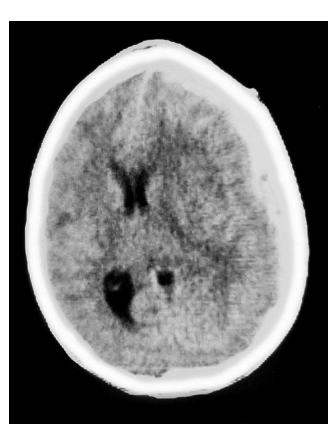

Paciente de 68 anos, previamente hígido, sem comorbidades, da entrada no PS trazido pelo SAMU, com história de queda do telhado ha meia hora. No atendimento inicial, na sala de emergência, paciente com PA 80x50 mmHg, FC 112, Glasgow 5. Colocado sob ventilação mecânica, recebendo droga vasoativa em cateter venoso central, coletados exames, foi encaminhado a Tomografia:

A tomografia evidenciou Hematoma Subdural Agudo, com efeito de massa, compressão ventricular e desvio de linha média.

Contactada equipe da neurocirurgia que, após avaliação especializada, indicou cirurgia de emergência para descompressão. Iniciado tambem, anticonvulsivantes, ainda na sala de emergência. Após cirurgia, paciente foi encaminhado a UTI para cuidados de pós-operatório. Permaneceu estavel por 3 dias, ainda sob ventilação mecânica. Recebeu apenas 24 horas de profilaxia cirúrgica com cefuroxima. No 3º PO, evoluiu com crises convulsivas e febre; submetido a nova TC de crânio que mostrou discreto edema e status pós-operatório. Houve piora da leucocitose no hemograma bem como aumento no PCR Coletado líquor que mostrou: 1540 celulas, predomínio de neutrófilos 80%, glicorraquia 37 e proteinorraquia 176.

Assinale a alternativa CORRETA com relação ao agente etiológico provavel e terapia antimicrobiana empírica: